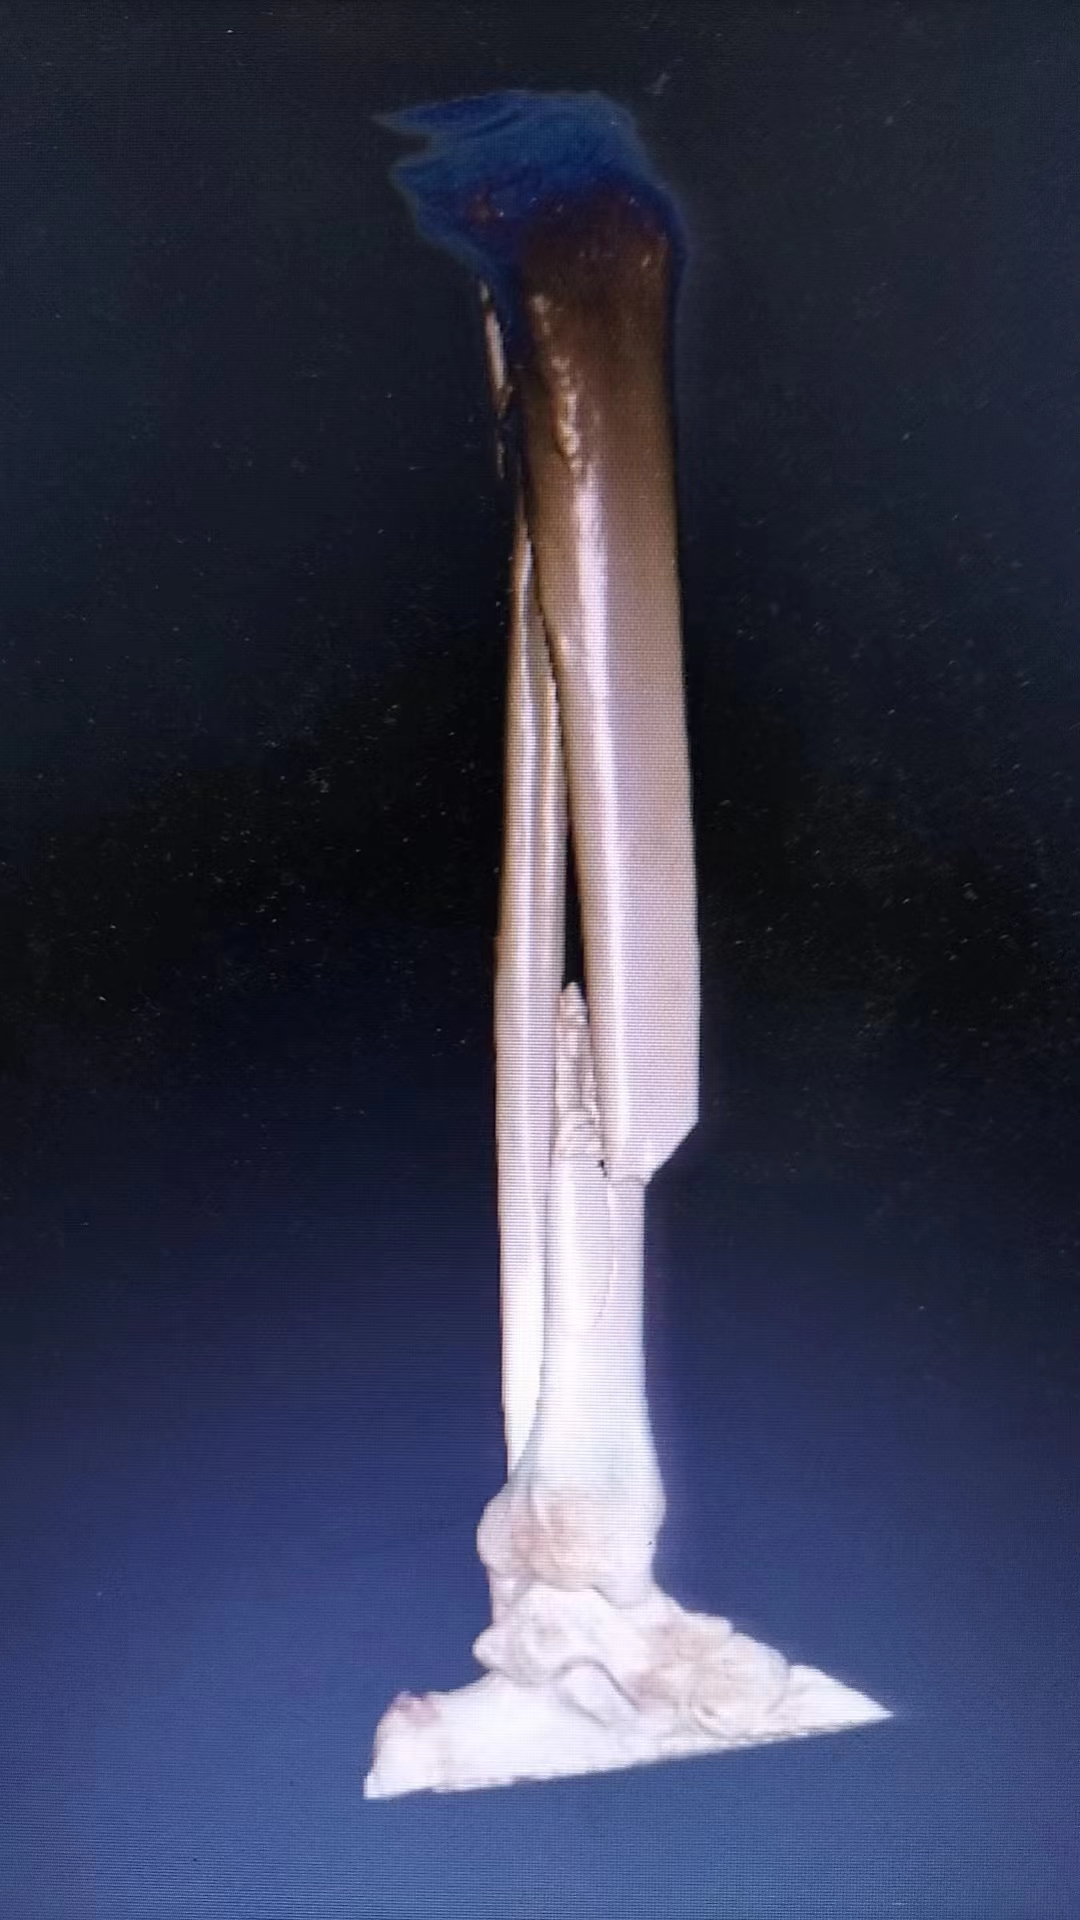

病例一:患者,女,70岁,车祸致左肱骨近端粉碎骨折,在孙院长组织术前讨论后决定行”左肱骨近端粉碎性骨折闭合复位髓内钉内固定术”考虑患者年龄大、基础病较多,微创治疗恢复快,骨三科医疗团队为其行手术治疗,术后功能恢复良好,患者及家属十分满意。 ▲术前 ▲术后 病例二:患者,男,51岁,因滑倒摔伤致左胫腓骨骨折伴后踝骨折,术前准备钢板内固定、髓内钉闭合内固定两种手术方案,通过术前讨论和局部皮肤条件的观察,选用髓内钉闭合复位内固定,骨三科医疗团队主刀下运用多枚克氏针(阻挡+固定+合拢),解决后踝和螺旋劈裂骨折块问题,手术顺利结束。 ▲术前 ▲术后 ▲术后 ▲术后微创小切口 目前,我院骨三科医疗团队已成功完成数例髓内钉手术,临床疗效非常满意。近年来周口人合医院骨三科大力发展微创技术,积极开展各类微创手术,力求打造微创以及快速康复的治疗新标杆,更好地为人民健康保驾护航。 ▲创伤与手足显微外科专家查房查看患者病情 ▲创伤与手足显微外科专家共同探讨患者病情